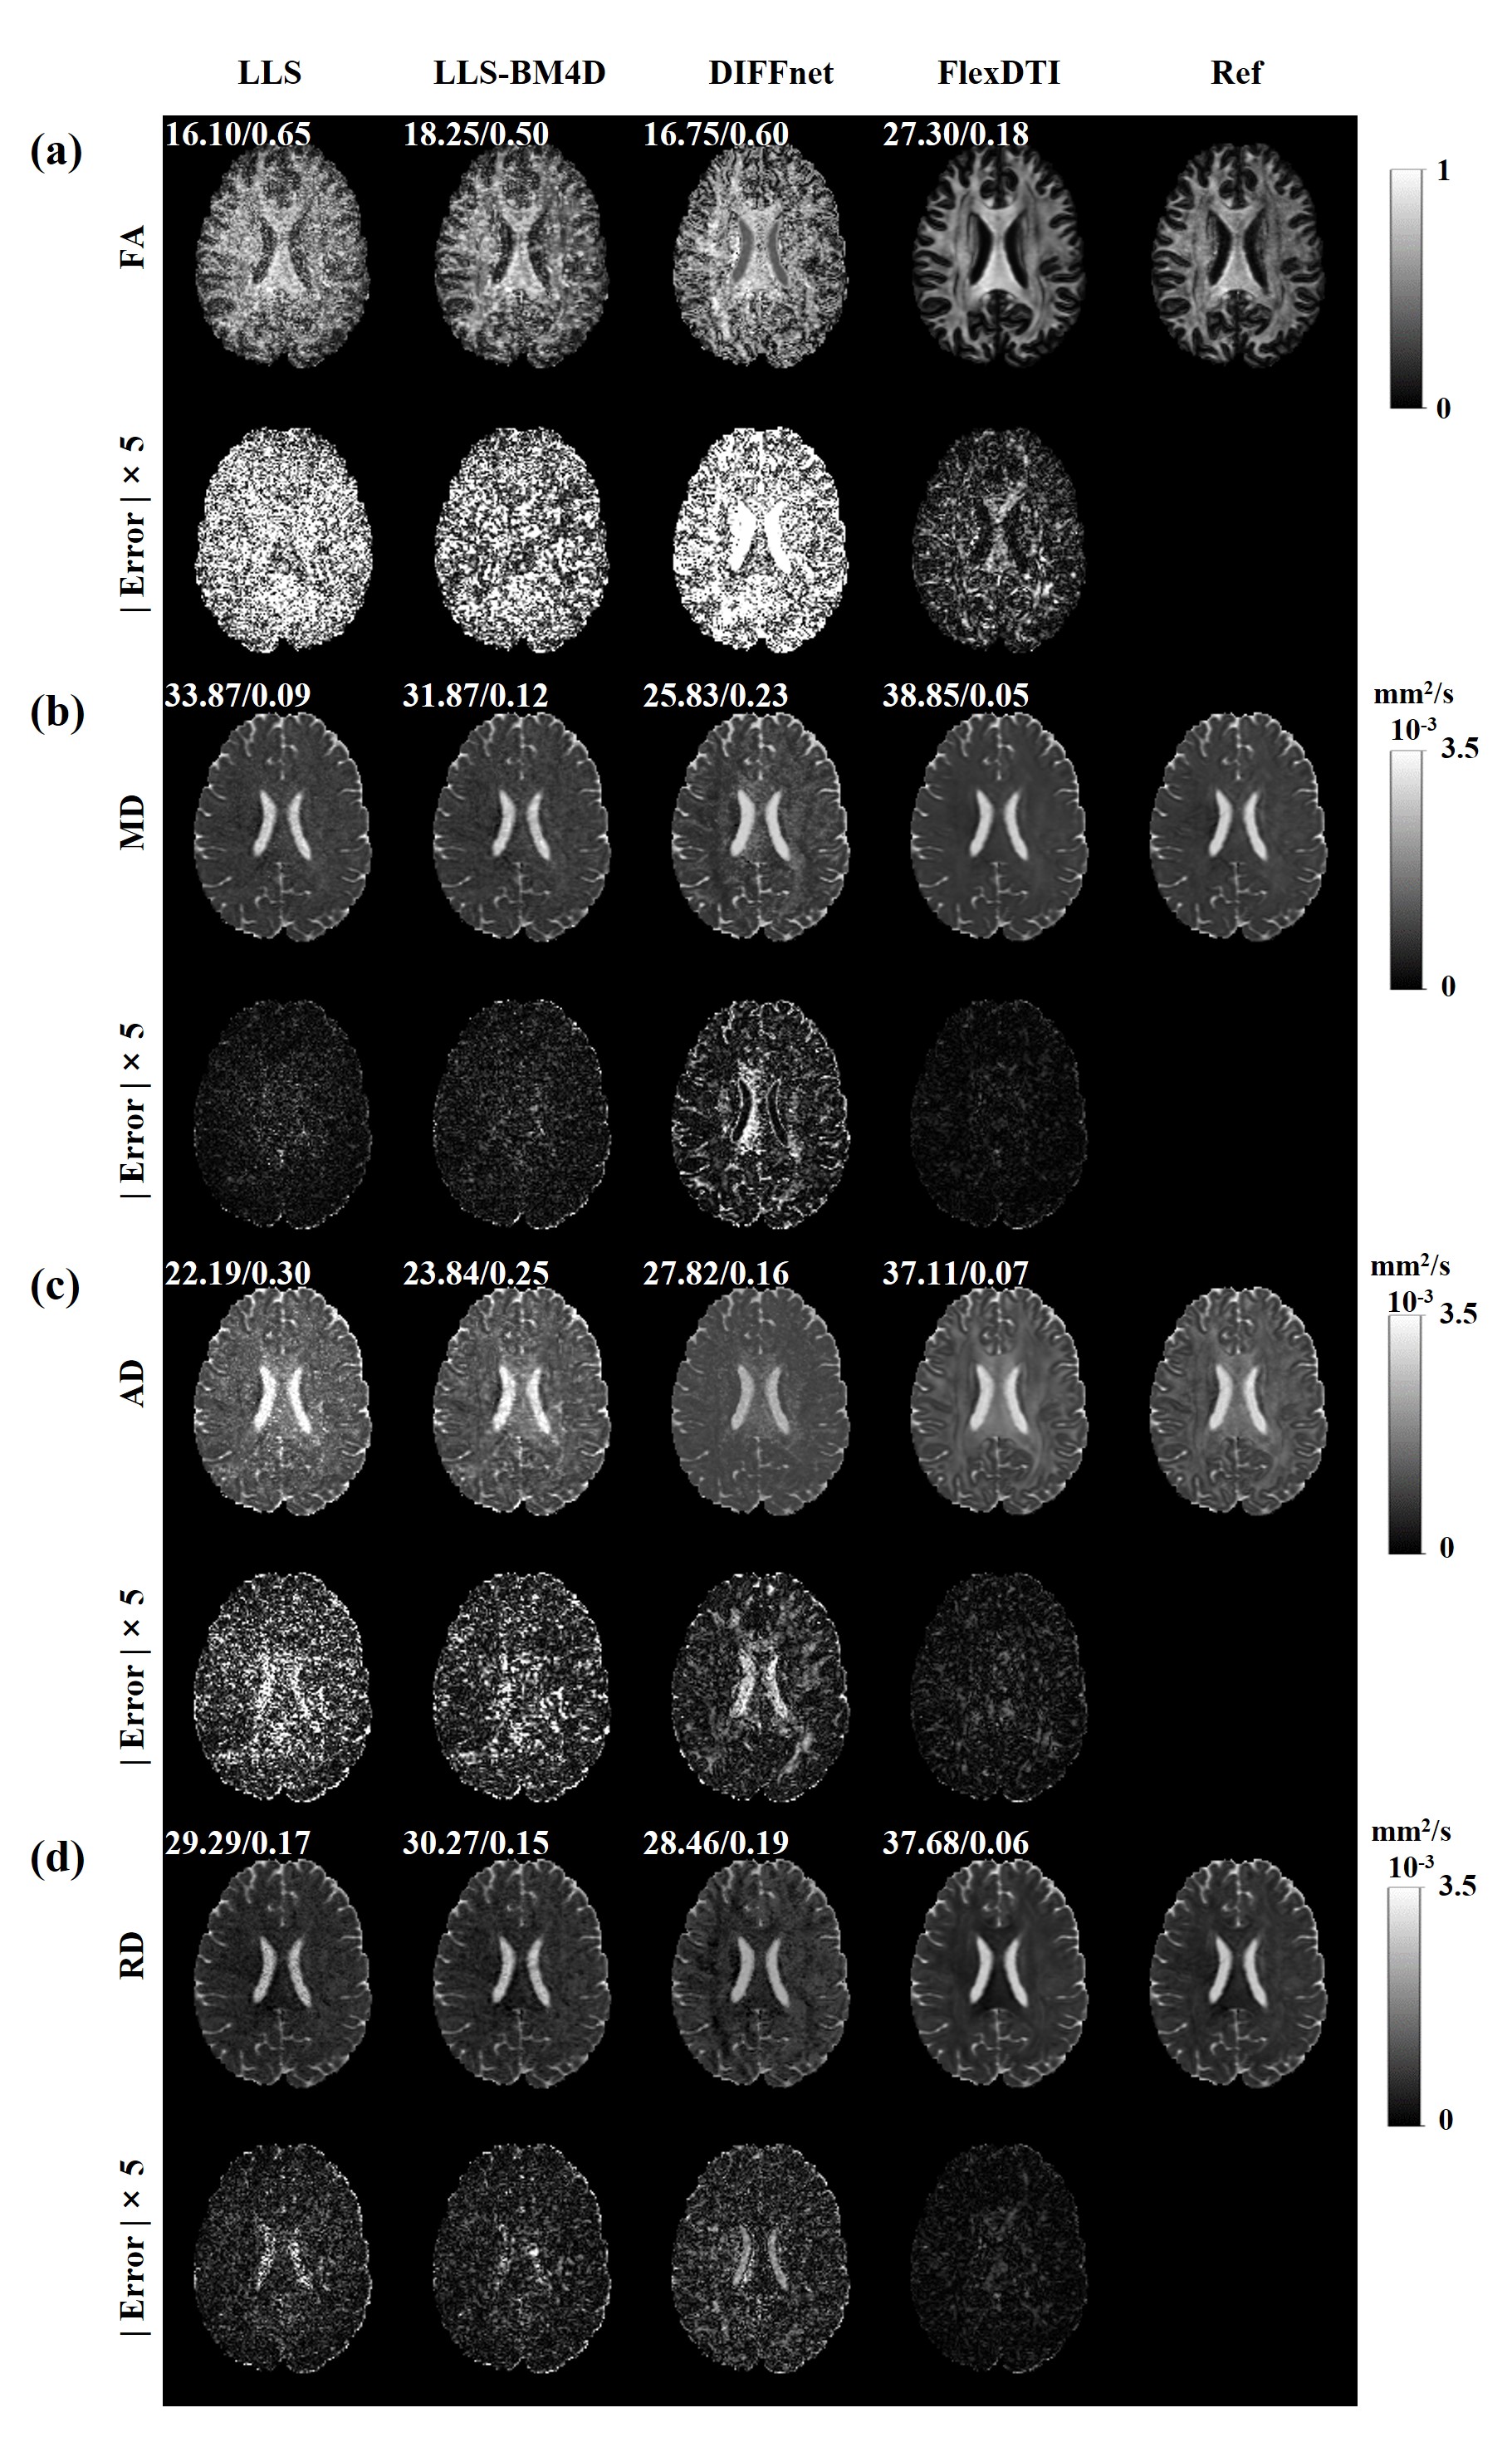

The results of four estimated tensor-derived parameters, i.e., FA, MD, AD and RD through different reconstruction methods were provided in Figure 2, where 6 DW images with flexible diffusion gradient directions were involved in the reconstruction. In terms of the reconstruction quality of the four quantitative parameters, FlexDTI has significant performance improvement compared with the other methods. The images from FlexDTI appear less noisy than others, with details more similar to the reference images. It is worth pointing out that 6 DW images are not sufficient to reconstruct high-quality DTI for DIFFnet method, while the proposed method can achieve high-quality DTI quantitative maps using only 6 DW images with flexible diffusion gradient directions.

Figure 2: Four parametric maps (FA, MD, AD and RD) reconstructed by LLS, LLS-BM4D, DIFFnet and FlexDTI using 6 DW images with flexible diffusion gradient directions. The references were reconstructed by LLS using 90 DW images. The PSNRs and NRMSEs are given at the upper left corner of each reconstruction image.

Table 1 presents the mean ± standard deviation of PSNR, SSIM and NRMSE for the data collected from 21 volunteers. These metrics correspond to the four estimated tensor-derived parameters obtained through four different methods. Compared to DIFFnet, FlexDTI reduces NRMSE by 0.54, increases PSNR by 8.15 dB and SSIM by 0.17 on FA, and reduces NRMSE by 0.17, increases PSNR by 10.36 dB and SSIM by 0.05 on MD.